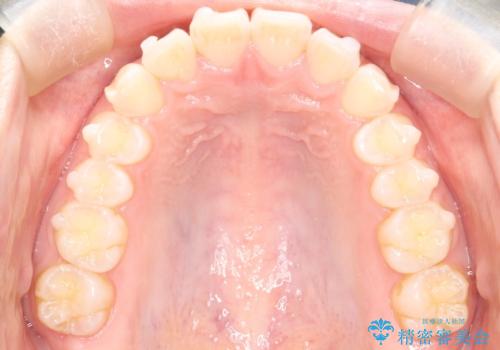

【インビザライン】前歯が出ているのを治したい

- 前歯が出ていることを主訴に来院されました。

前歯の突出感が改善され、満足していただきました。